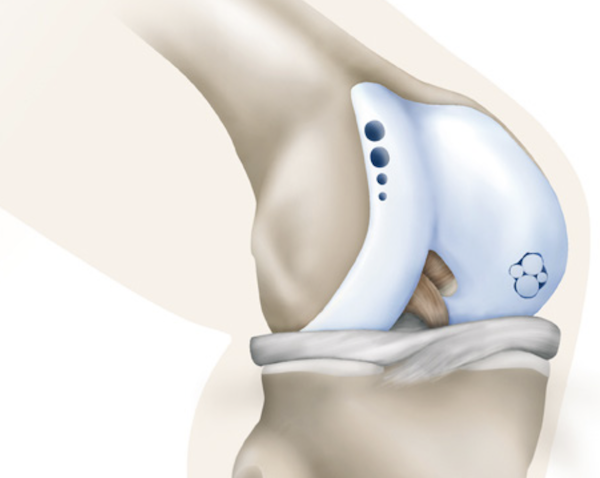

Membrangestützte Knorpelgeneration

(autologe matrixinduzierte Chondrogenese, AMIC)

Knorpeltherapie mit Membran in einer Operation. Die Membran wird in den Knorpeldefekt eingebracht, nachdem dieser angebohrt wurde, um das Einwandern von Stammzellen zu ermöglichen (siehe Abb. 2). Die Stammzellen können langfristig neues Knorpelgewebe aufbauen.